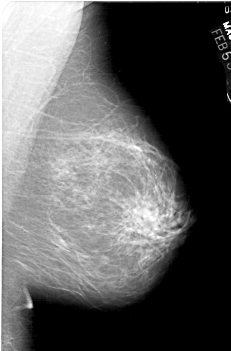

A_1443_1.RIGHT_MLO

RIGHT_MLO LINES 5956 PIXELS_PER_LINE 3916 BITS_PER_PIXEL 12 RESOLUTION 43.5 NON_OVERLAY